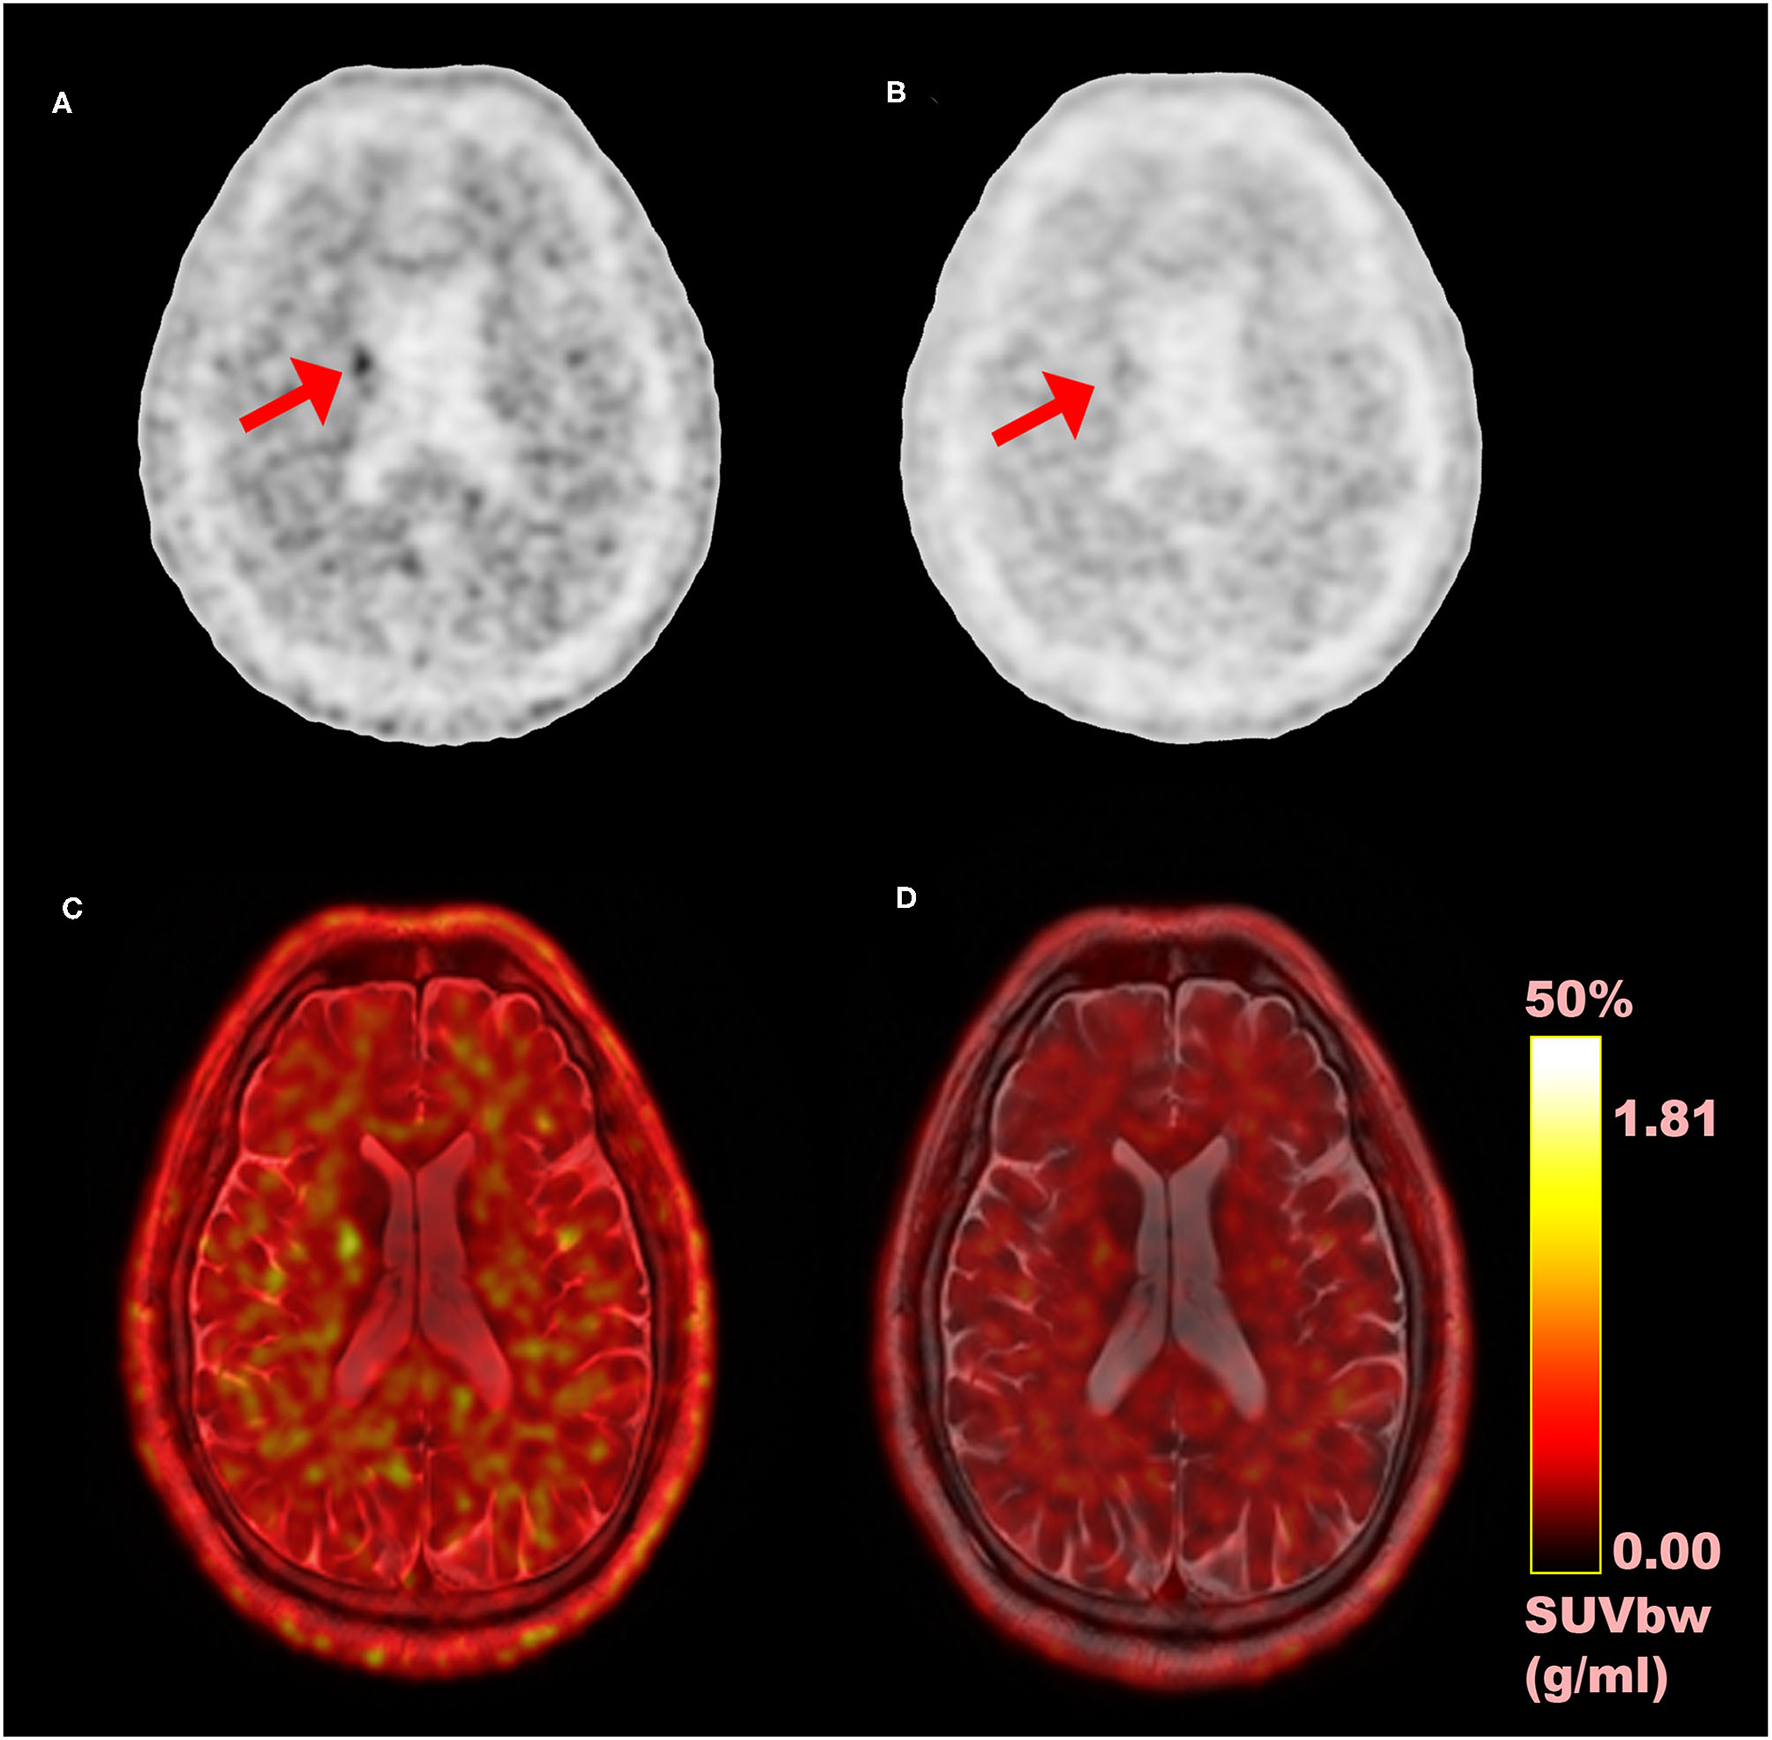

In the study, we evaluated the magnitude of quantitative difference produced by TOF reconstructions on CN and PU VOIs for short-lived 11C-CFT brain PET and further compared with the same VOIs with 11C-PiB for any correlation of TOF effect with a different short-lived tracer. Apparently, varying uptake properties of different VOIs caused a considerable impact on the TOF effect; however, the TOF effect has a consistent association with SUVmean rather than SUVmax values in both VOIs between 11C-CFT and 11C-PiB. Significantly enhanced SUVmean among segmented VOIs of both radiotracers confirmed that TOF facilitates short-lived radiotracers over non-TOF reconstruction. Moreover, the whole-brain, which is investigated due to its diffuse 11C-PiB uptake qualities, spotted significantly enhanced SUVmax, SUVmean, contrast, and SNR. It is observed that quantitative differences of image quality parameters vary among CN and PU with their uptake characteristics relative to the selected reference region. To the best of our knowledge, it is the first time that different tracers of short-lived 11C for brain quantitation imaging were performed with TOF and non-TOF PET/MRI. Overall, the experiment revealed that TOF reconstructions significantly affect SUVs compared with non-TOF and further improved the image contrast and SNR for a considerable extent, which proposed the TOF technique with higher time resolution (lesser than 400 ps) that contributes in achieving the optimal performance reconstruction of brain PET images with short-lived 11C-labeled tracers (Figure 4). Thus, it is recommended to consider the quantitative difference caused by TOF PET/MR modalities while diagnosing AD/PD.

Figure 4

Comparison of time-of-flight (TOF) vs. non-TOF 11C-PiB PET images; (A) TOF reconstructed PET image (axial plane); (B) non-TOF reconstructed PET image (axial plane); (C) fusion image of TOF PET and MRI; (D) fusion image of non-TOF PET and MRI; red arrows: shows the signal enhancement difference in TOF and non-TOF PET images in 11C-PiB PET images.